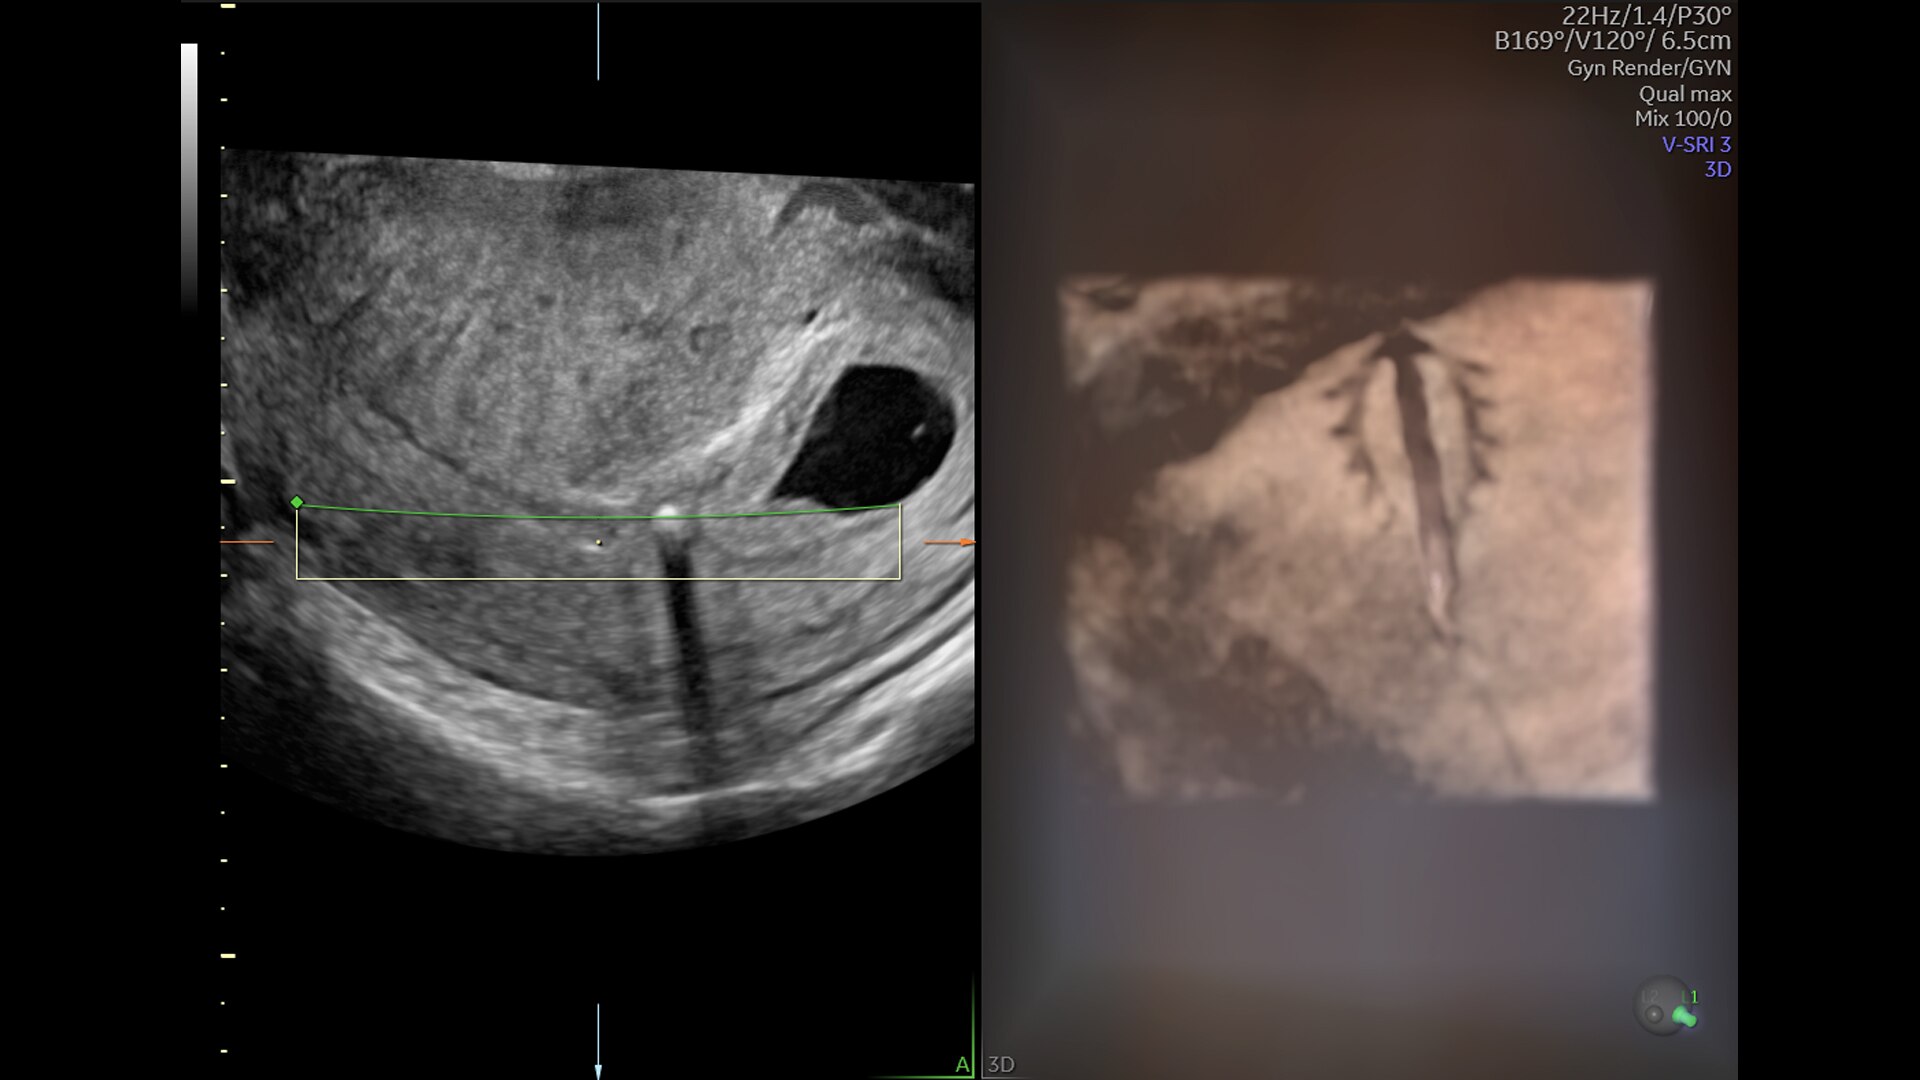

Pelvic Health

Offer patient answers faster with Ai-based automation tools